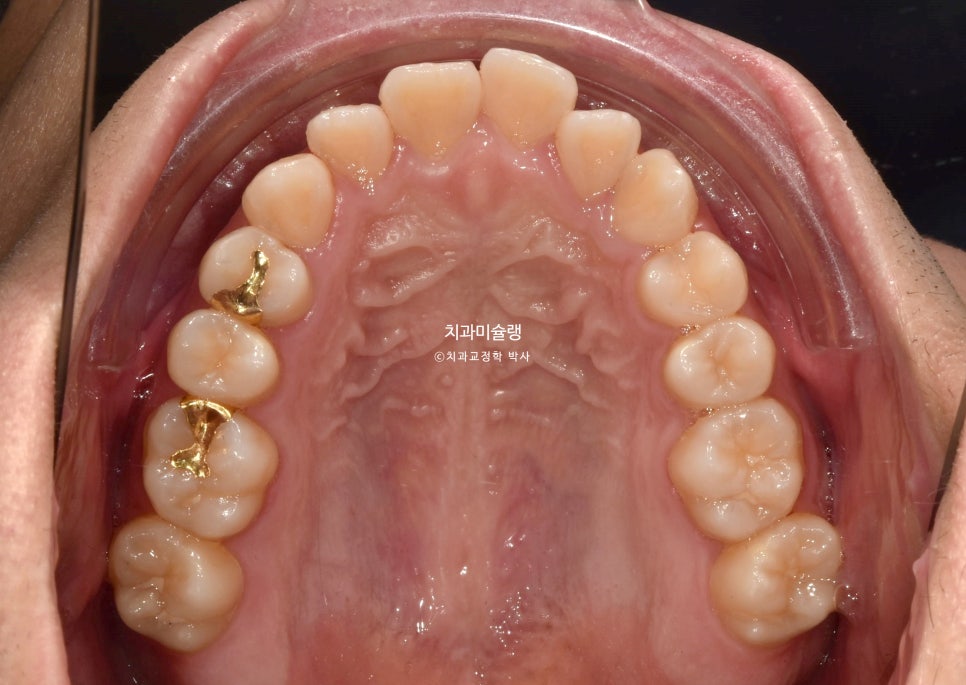

초진 시 구강 상태

2024년 봄 초진

2024년 봄 교정치료를 위해 내원한 환자분 입니다.

중심선 불일치, 반대교합, 덧니 등이 보입니다.

앞니가 뻗친 돌출 입니다.

그에비하면 어금니는 배열도 좋고 교합도 좋은 편이죠.

입이 잘 안다물어질 정도의 돌출입이며 웃을때 잇몸이 과하게 보이는 거미스마일도 있습니다.

입 다무는게 편치 않아서 턱끝에 자갈턱 또는 호두턱이 생길 정도의 돌출입 이라면 작은어금니 4개 발치교정이 필요합니다.

병원에 자주 못오는 환자분의 사정을 고려하여 인비절라인 교정 권유드렸습니다.